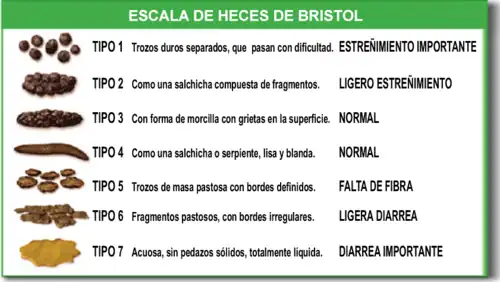

Ninguno de los métodos que se emplean hasta la fecha (2018) para evaluar el cumplimiento estricto de la dieta sin gluten es objetivo ni fiable: cuestionarios rellenados por los pacientes, evaluación de los síntomas, determinación de los anticuerpos específicos de la celíaca y hallazgos en las biopsias duodenales.[10][80][89] Ni la ausencia de síntomas digestivos, ni la negatividad de los anticuerpos garantizan que exista una recuperación de la mucosa intestinal, cuya valoración mediante las biopsias es complicada.[10][11] Esto se debe a que las lesiones del intestino suelen consistir en cambios mínimos, sin atrofia de las vellosidades, difíciles de identificar.[10] Desde 2017 está disponible un nuevo método basado en la detección de gluten en muestras de orina o heces para uso profesional y desde enero de 2018 en versión para uso doméstico, que ha demostrado su eficacia en estudios científicos para controlar el cumplimiento de la dieta y detectar contaminaciones por trazas.[10][90]